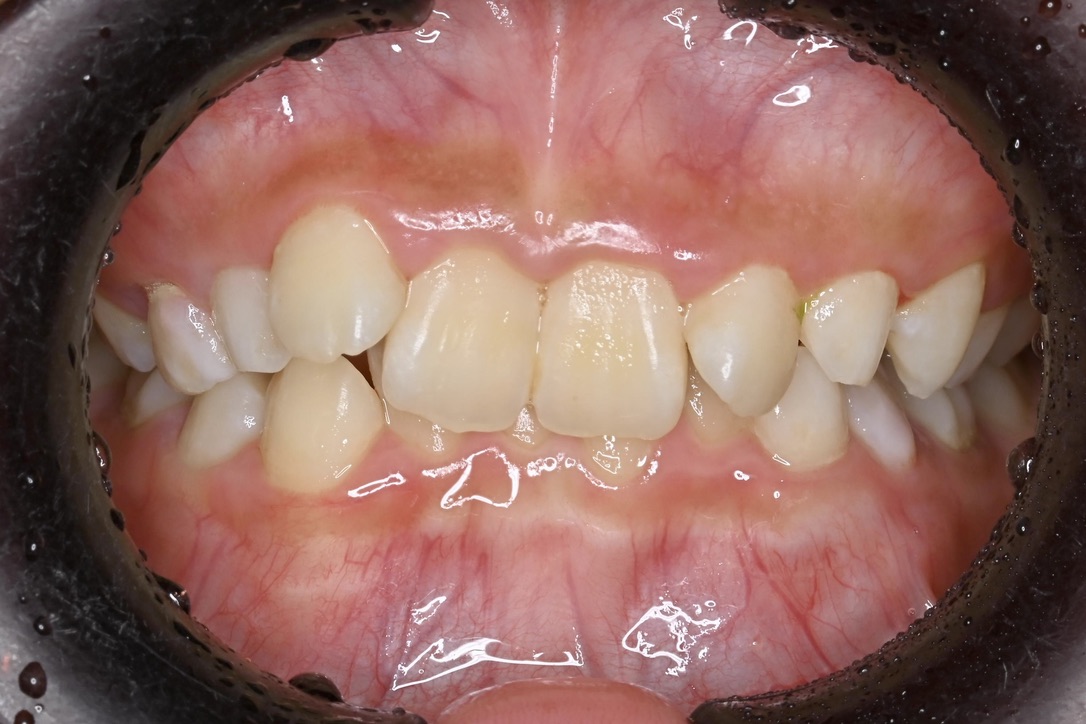

乳歯と永久歯が混在する6歳頃〜11歳

乳歯と永久歯が混在する時期に行う矯正歯科治療です。

顎や口腔機能の成長・発育といった「土台」から正しい歯並びへ導く、お子様ならではの矯正治療が行えます。

負担を考えた、お子様一人ひとりに適切な装置を使用します。